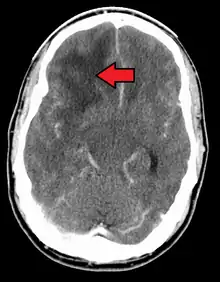

When viewed with MRI, glioblastomas often appear as ring-enhancing lesions. The appearance is not specific, however, as other lesions such as abscess, metastasis, tumefactive multiple sclerosis, and other entities may have a similar appearance.[53] Definitive diagnosis of a suspected GBM on CT or MRI requires a stereotactic biopsy or a craniotomy with tumor resection and pathologic confirmation. Because the tumor grade is based upon the most malignant portion of the tumor, biopsy or subtotal tumor resection can result in undergrading of the lesion. Imaging of tumor blood flow using perfusion MRI and measuring tumor metabolite concentration with MR spectroscopy may add diagnostic value to standard MRI in select cases by showing increased relative cerebral blood volume and increased choline peak, respectively, but pathology remains the gold standard for diagnosis and molecular characterization.